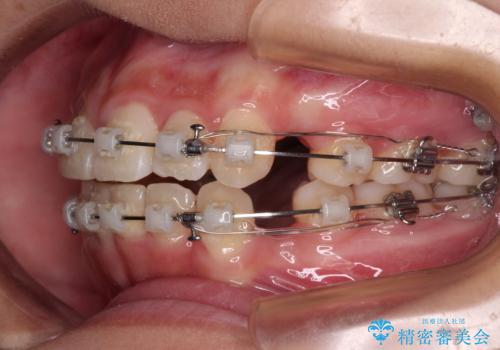

上顎骨幅が狭い 急速拡大装置を併用した抜歯矯正

検査を行った結果、上顎骨の横幅が相対的に狭いことが分かり、叢生が強いことから、急速拡大装置にて上顎骨を側方に拡大することで、叢生の解消と奥歯の咬み合わせ改善を図ることとしました。

一般的には上下左右の第一小臼歯4本を抜歯する必要がありますが、拡大量によっては非抜歯矯正の適用となる可能性があるため、まずは非抜歯矯正で治療を開始し、抜歯が必要と判断された時点で速やかに4本抜歯を行うこととしました。

急速拡大後、歯列はきれいに並んだのですが、口元が出っ歯になってしまったため、速やかに抜歯を行い、治療期間がいたずらに遅延することのないようにしました。